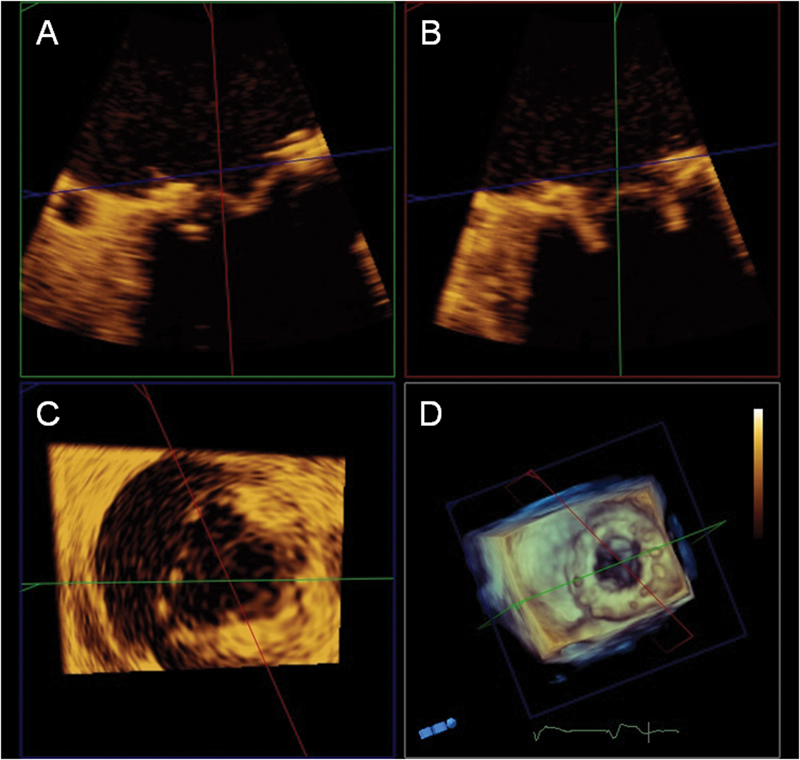

فحوصات تشخيصية لبعض امراض القلب والشرايين التاجية